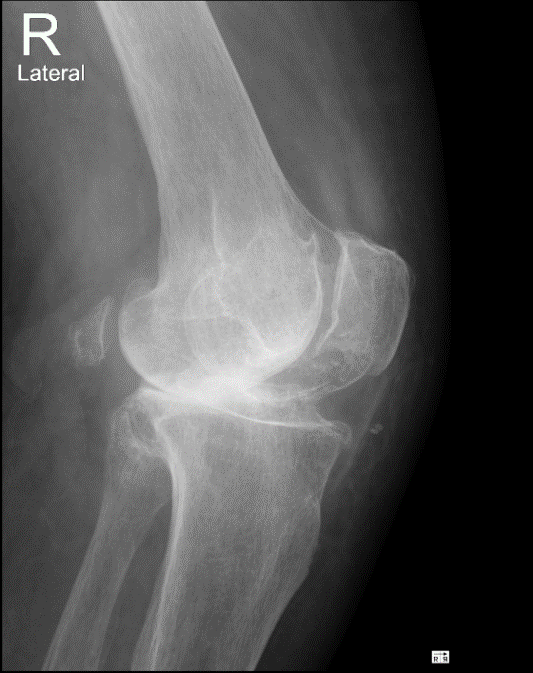

Клинический пример №3.

Правосторонний гонартроз Rg III ст. Смешанная контрактура правого коленного сустава НФ 3 ст. Дефект медиального мыщелка большеберцовой кости. Genu varum.

После тотального цементного эндопротезирования коленного сустава эндопротезом.